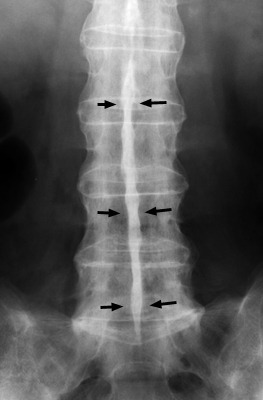

'대나무 척추(Bamboo spine)'라는 용어는 인대증식체(섬유륜의 골화)의 과도한 증식의 존재로 특징지어질 수 있다. 트롤리-트랙(Trolley-track) 징후는 전방 방사선 영상에서 보이며, 극상인대와 극간인대와 골단관절낭의 골화와 일치하는 세 수직 방향의 치밀한 선을 의미한다. 트롤리-트랙(Trolley-track) 징후는 극상인대와 극간인대의 골화를 나타내는 전방 방사선 영상에서 단일 방사선 라인으로 나타나는 단검 징후(dagger sign)에 비해 앞설 수 있다.

△ Dagger Sign

(이미지 출처 : http://www.gentili.net/signs/34.htm)